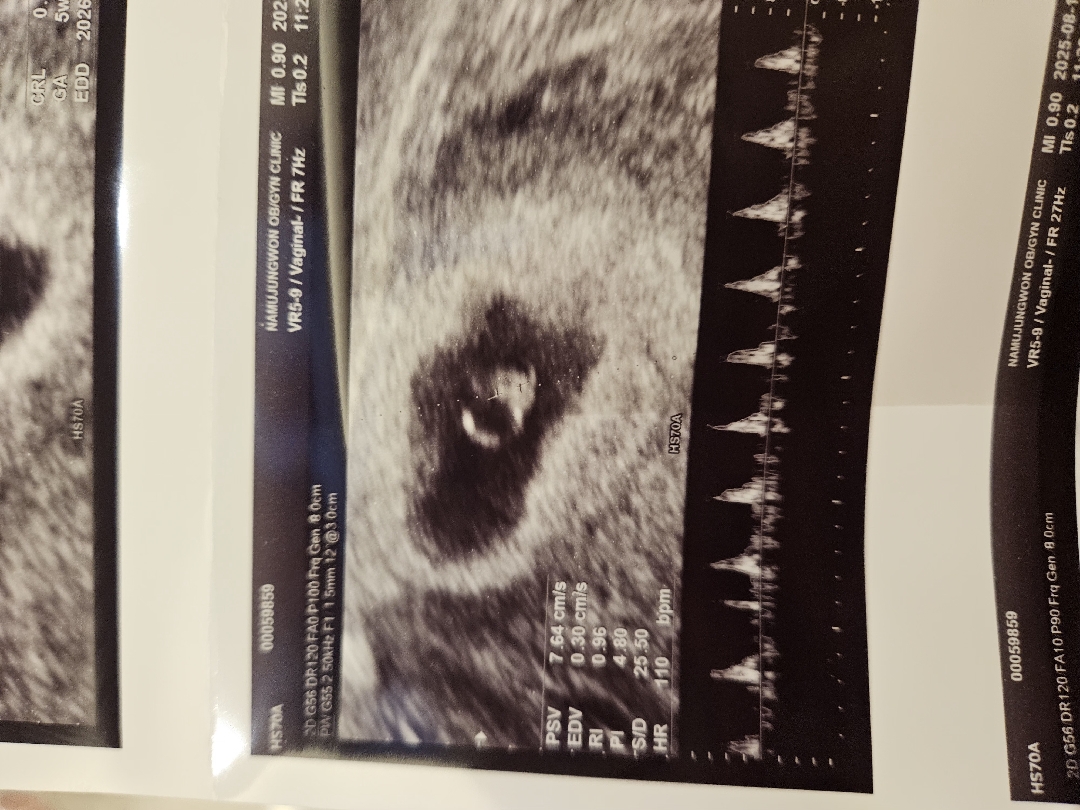

6주1일차 이구. 오늘 심장소리듣고왔네요 규칙적이고 잘 뛴대요 ㅎㅎ 아기가 작아서 120bpm이 아니고110bpm이라는데 아기는 천천히 클거라고 믿구 너무기특해서요 🥺🥺광광 울었어요

저두 6주1일차에 듣고 왔어요 110bpm 정상이라고 하시던데요?❤️🔥☺️